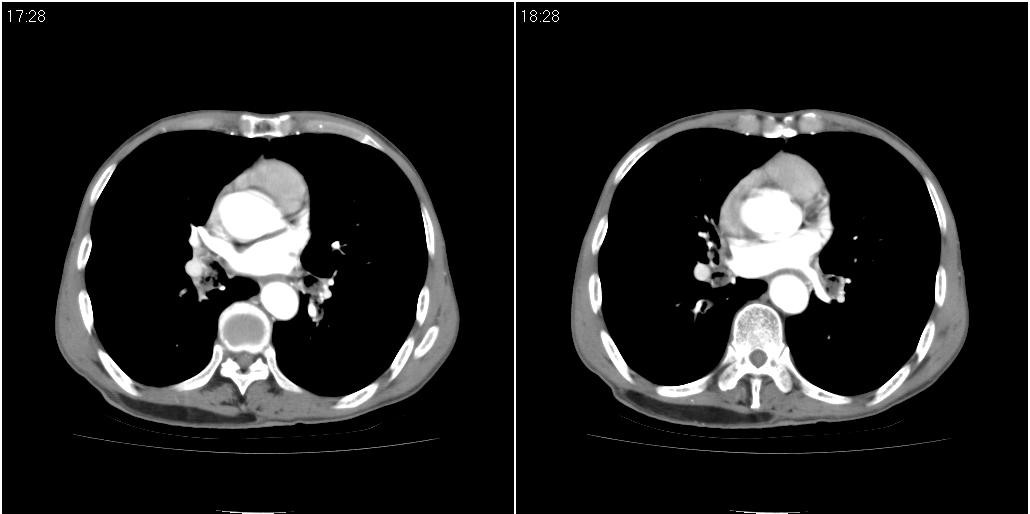

标题: CT25416:男性,70岁。胸片发现右下肺斑片状阴影

以下是ct检查的情况:

标题: ct增强:

考虑右肺下叶炎症可能性大?未除占位,建议增强。右下肺肺不张

右肺中叶阻塞性不张及肺炎,高度怀疑支气管占位,建议纤支镜检查!

1)右肺中叶慢性炎症并支气管扩张,节段性肺不张。2)两肺下叶支气管扩张。